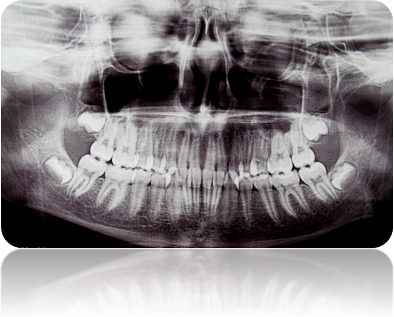

Медицинские Исследования: Кортикальная Пластинка на ОПТГ